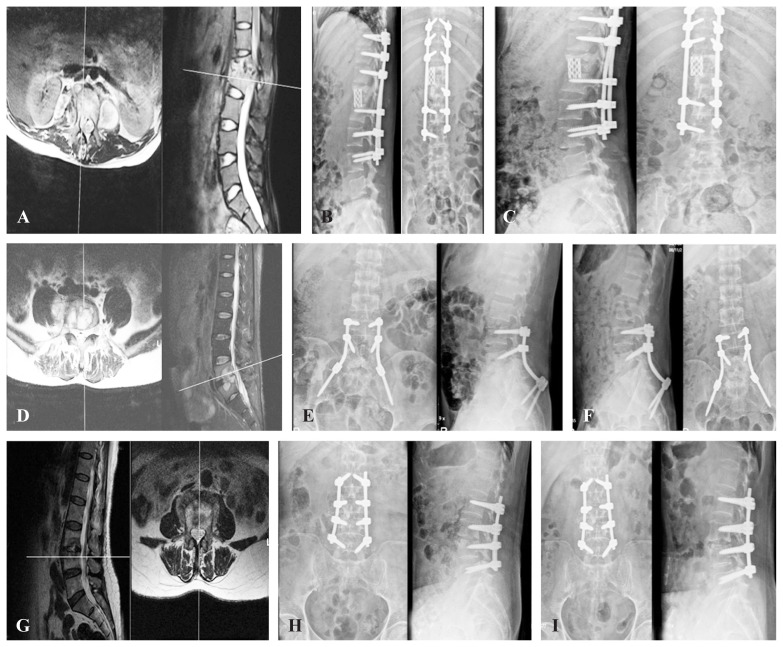

Abstract Image